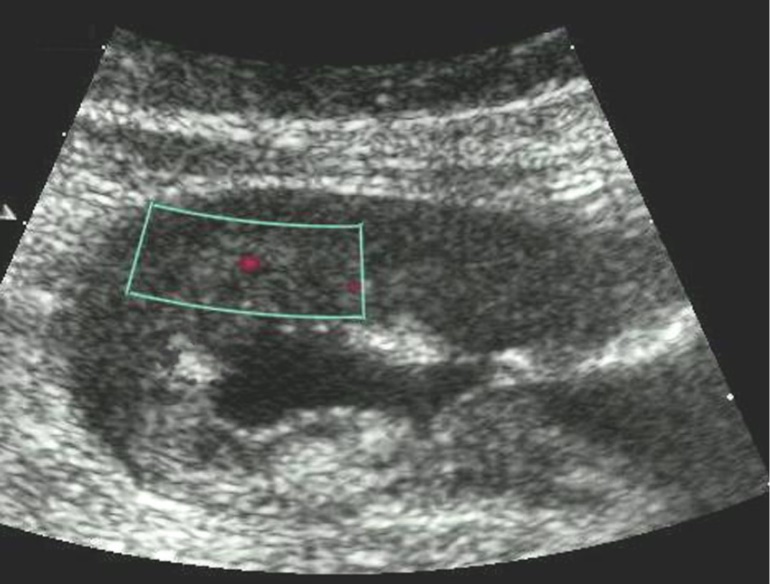

Color Doppler mode was used to assess the nature of the gastric wall lesion in pathologically thickened areas. This method allows the recording of blood flow in the altered areas and using the degree of vascularization to differentiate gastric cancer and other benign changes. Usually in a normal gastric wall it is not possible to visualize the vessels.

Among the 61 patients, pathological vascularization was detected in 42 (68.8%) cases. Of these, all 4 (6.5%) patients with gastric cancer were stage T4 and 38 (62.3%) were stage T3. In 13 cases, vascularization was weak, in 24 cases - moderate, and in 5 cases - enhanced.

Weak vascularization was manifested in the form of a single point color vascular signals, the moderate vascularization - in the form of linear color vascular signals and the enhanced vascularization - in the form of wide color areas inside the tumor (Figure 16, Figure 17).

Figure 16.Distal gastric carcinomas of diffuse infiltrative form of T4 stage. Despite the large size of the tumor the vascularization is manifested in the form of single point color vascular signals.